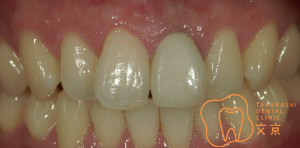

■前歯を治したい。 オールセラミックスによる審美治療

■前歯を治したい。40代男性 オールセラミックスによる審美治療

■前歯を治したい 精密審美治療・セラミックス治療

■前歯 精密審美治療

■前歯のセラミックス治療 審美治療

■前歯のオールセラミックス治療

■保険の前歯を直したい